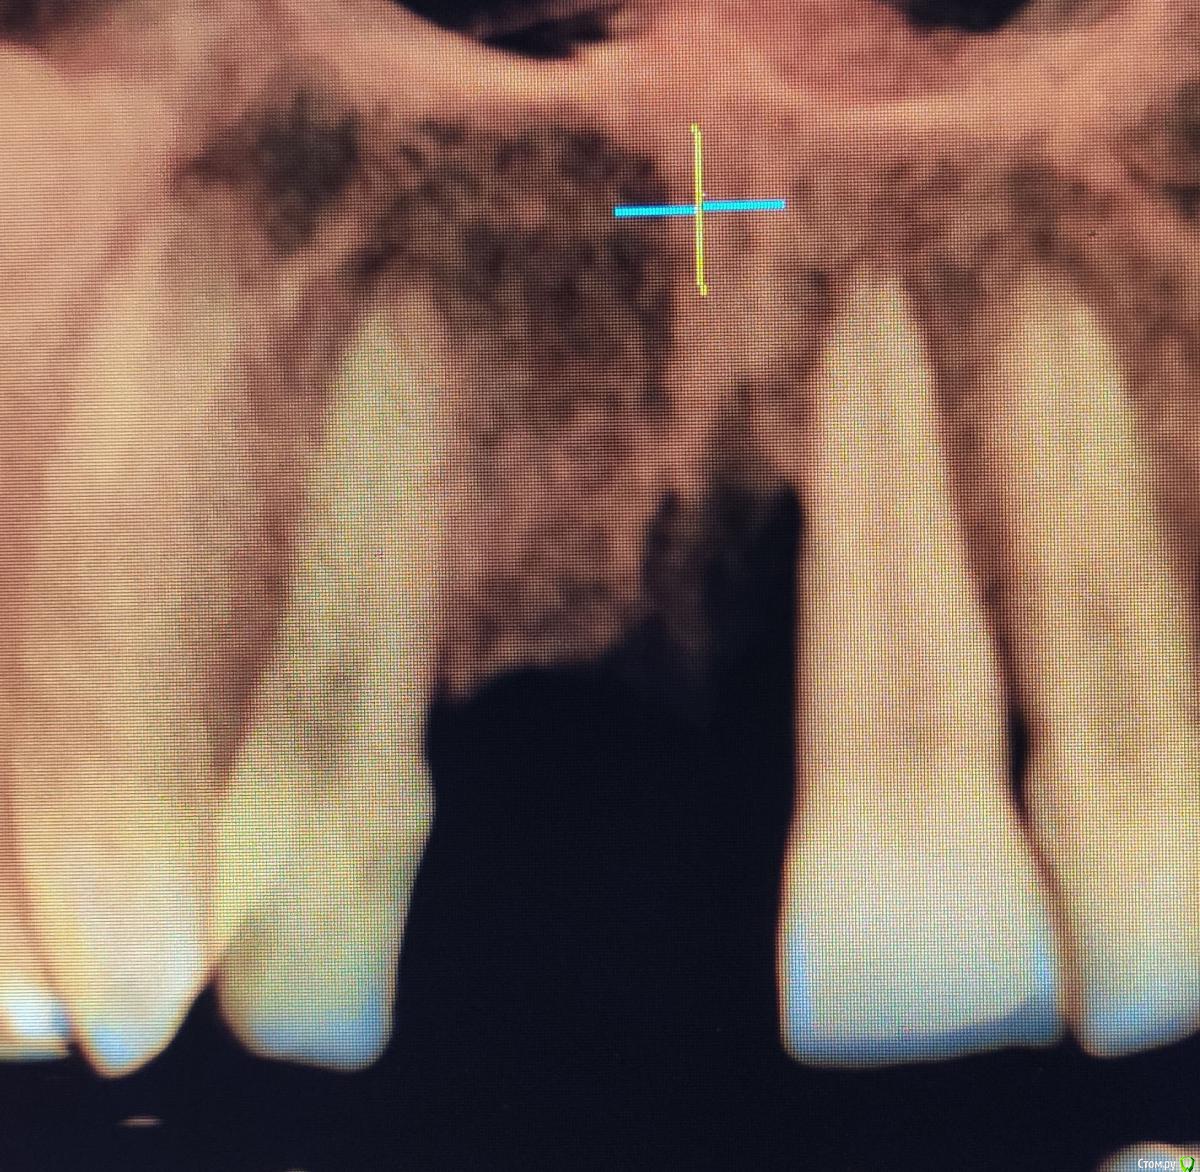

Bier Опубликовано 31 января, 2020 Поделиться Опубликовано 31 января, 2020 после удаления какие варианты лечения? надо же кость наращивать?смотря какие требования по эстетике. Нужны фотографии, КТ Ссылка на комментарий

red_butler Опубликовано 31 января, 2020 Поделиться Опубликовано 31 января, 2020 по эстетике никаких требований, главное долговечность и чтобы кость дальше не уходилапокажите фото, что бы было видно зубы и десну. и сделайте Кт Ссылка на комментарий

andrewV Опубликовано 3 марта, 2020 Автор Поделиться Опубликовано 3 марта, 2020 (изменено) покажите фото, что бы было видно зубы и десну. и сделайте Ктhttps://yadi.sk/d/ni1dhoFNU0ns3A КТ из пикассо Изменено 3 марта, 2020 пользователем andrewV Ссылка на комментарий

andrewV Опубликовано 3 марта, 2020 Автор Поделиться Опубликовано 3 марта, 2020 (изменено) В одной из клиник предложили удалить единичку с кистой и обточить двойки под коронки, на них же можно будет повесть временный протез, пока будут приживаться импланты и костная ткань. Можно ли как-то обойтись без обточки, но не ходить 3-4 месяца без передних зубов? Почему-то ничего не сказали насчет кариеса корня на двойке, его же надо депульпировать в таком состоянии? Изменено 3 марта, 2020 пользователем andrewV Ссылка на комментарий